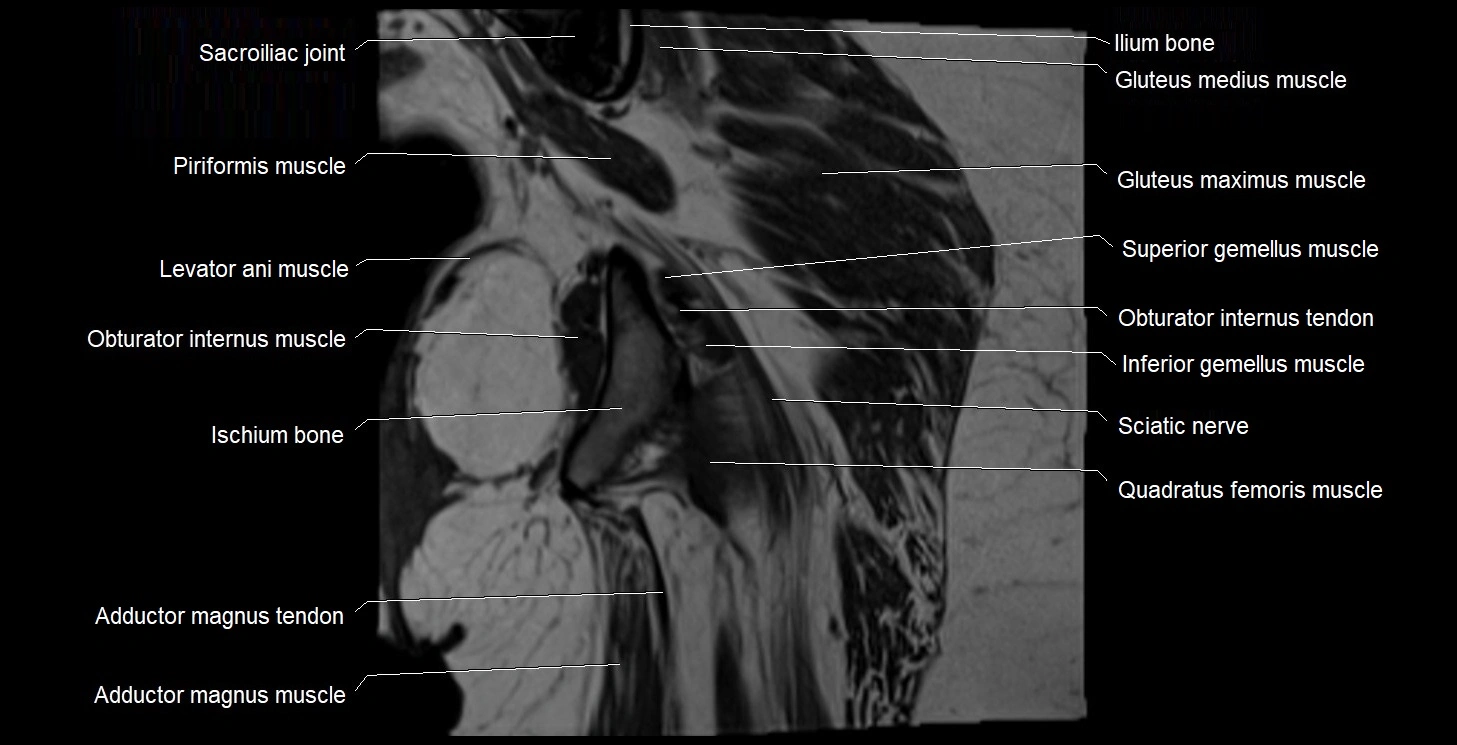

- Adductor magnus muscle

- Adductor minimus muscle

- Inferior gemellus muscle

- Ischium bone

- Levator ani muscle

- Obturator internus muscle

- Obturator internus tendon

- Quadratus femoris muscle